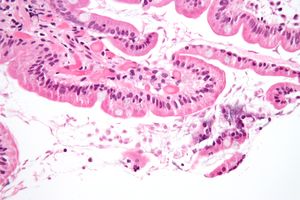

يتعلق طفيل الجيارديا بطبقة الظهارة في الأمعاء عن طريق قرص بطني لاصق و يتكاثر عن طريق الانقسام الثنائي.

لا ينتشر المرض الذي تسببه عن طريق الدم ولا ينتقل حتي إلي باقي أجزاء القناة الهضمية إذ يظل مقتصرا علي تجويف الأمعاء الدقيقة حيث يقوم طور الـ"تروفوزويت" للجيارديا بامتصاص المغذيات من تجويف الأمعاء وهو طور لاهوائي التنفس.

وهي وحيدات خلية تتطفل على الجهاز الهضمي العلوي وخاصة العفج و تسبب إسهالات بواسطة ارتباطها بالحجم على الزغابة المعوية للجهاز الهضمي . لها شكلين :

- ناشط : مثل شكل القرد Monkey Face)) له نواتان (يمنى و يسرى ) وله ثمانية سياط يتحرك بواسطتها .

بدراسة البراز الطازج ( خلال 1_2 ساعة ) نرى الجيارديا تتحرك داخل العينة حركتها مميزة متأرجحة (تشبه حركة تساقط أوراق الشجر ). أبعادها 30 ميكرون (وحيدات خلية ) البيوض (40_60) الكيس نصفه (10 ميكرون (غالباً الكيس حوالي النصف وتلك قاعدة عامة ) . الأكياس شكلها بيضوي لها نواتين مميزتين (يمكن أن تنقسما إلى أربعة في الكيس ) وفي المنتصف تتجمع السياط الخارجة داخل الكيس بشكل حرف S .